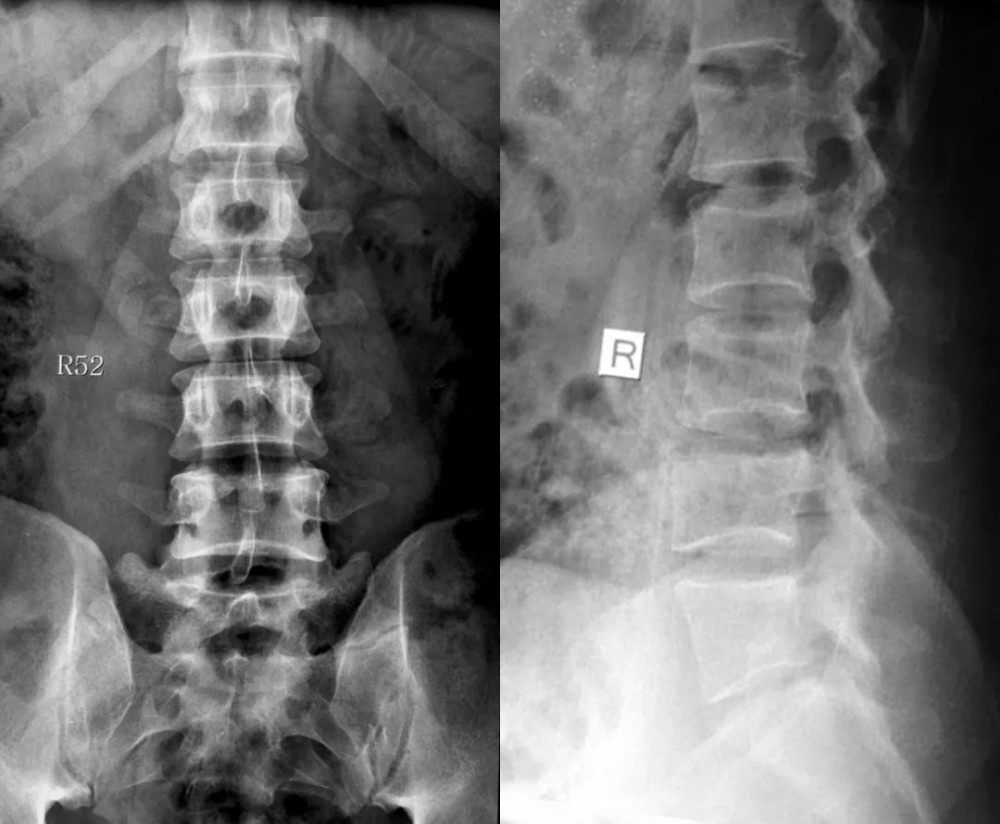

文章插图

红色箭头所指处为 L5 椎体双侧横突与骶骨骨性融合 , 为 Ⅲb 型

图解

此病例为骶椎腰化